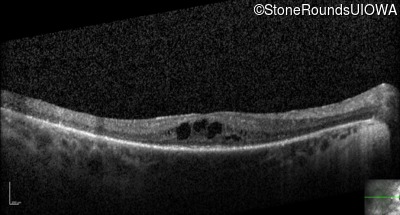

Optical Coherence Tomography - Left - 20/80 +2

Exemplar / OCT Stack